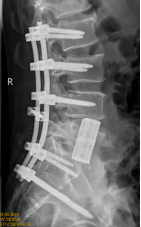

5.微创胸腰椎固定融合技术

微创胸腰椎固定融合技术适用于治疗腰椎间盘突出症、腰椎管狭窄症、腰椎失稳、腰椎滑脱、胸腰椎骨折、腰椎峡部不连及部分翻修手术等。其与传统TLIF技术相比,该技术通过最小的创伤即能达到和开放腰椎减压融合手术同样的临床效果,同时可减少并发症,实现病人快速康复的目的。